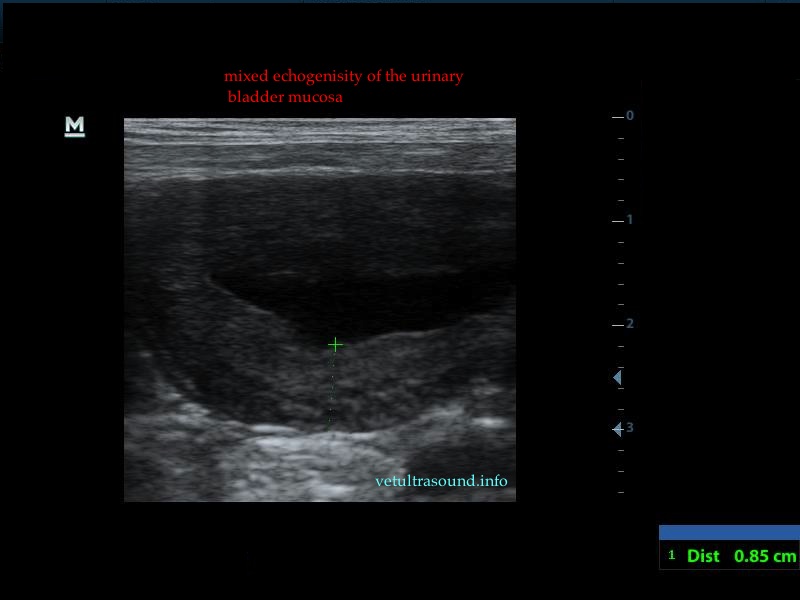

In all the following cases, urinary samples were taken for culture, in order to confirm the diagnosis of bacterial cystitis. In most cases the urinary bladder was almost empty due to polyuria, so we had to wait for about fifteen minutes, with or without the use of furosemide.

The increase of thickness of the urinary bladder wall and the striation of the mucosa is evident. Inguinal lymphnodes are usually prominent and mildly enlarged. Colour Doppler may reveal the blood flow of the mucosa of the empty urinary bladder, whereas the blood flow in a full bladder appears decreased. This could be because of the fibrosis of the urinary bladder wall and could explain why sometimes chronic conditions like these do not respond well to antibiotics. This pathophysiology has been studied in humans with the use of endoscopic ultrasound.